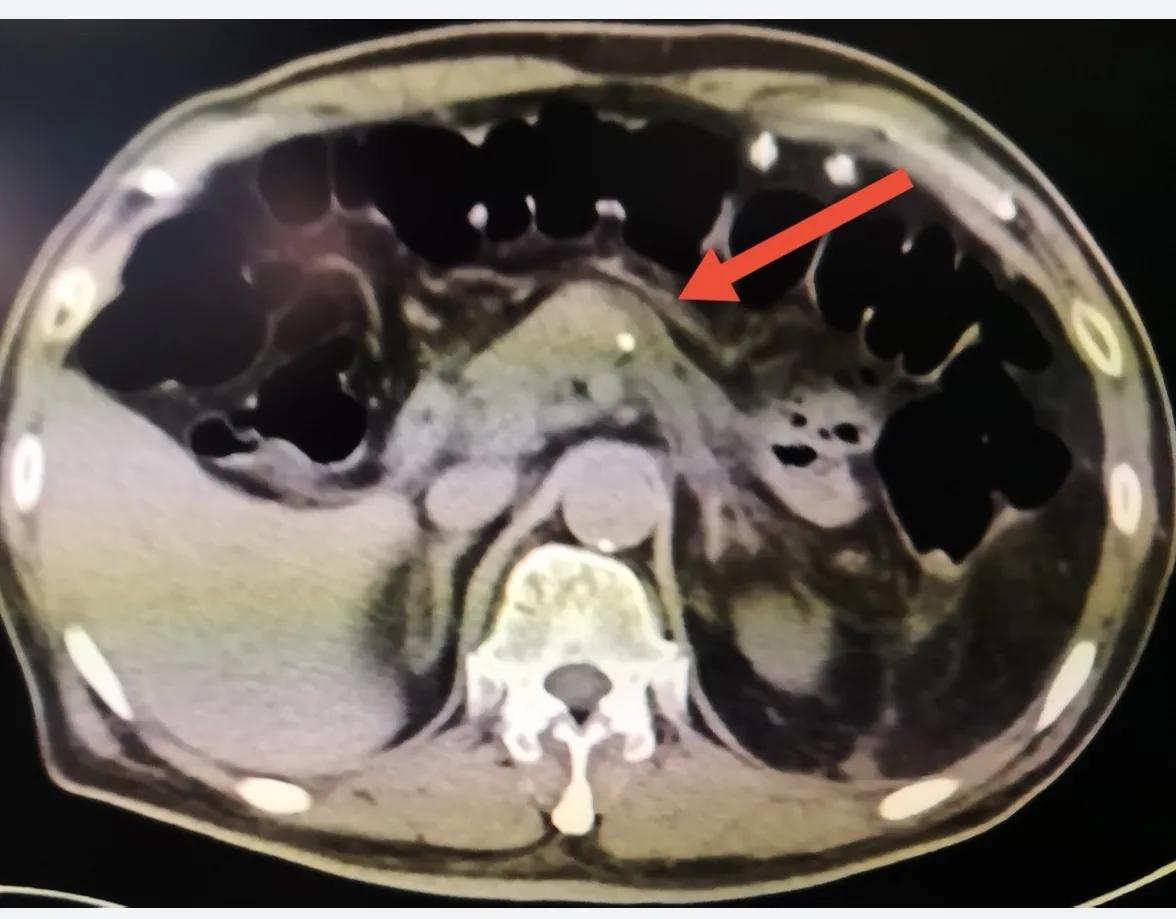

患者入院后行进一步检查,化疗检查肿瘤标记物CA-199 3500U/ml;腹部增强CT提示胰尾部囊实性占位,考虑恶性可能性大,未见明显肿大淋巴结;胃肠镜检查及心电图未见明显异常。

腹部增强CT见胰尾囊实性占位,箭头所示

增强CT下胰尾肿瘤